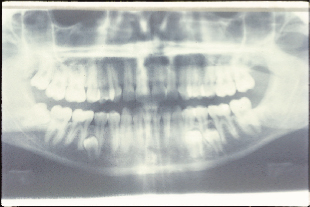

Hình 3: Phim toàn cảnh bệnh nhân đa răng dư |

Răng dư có thể xảy ra một hoặc nhiều răng, một phía hoặc hai phía, đã nhú ra hoặc còn ở mọc ngầm và ở một hoặc cả hai hàm. Đa răng dư là hiếm gặp ở cá nhân không có các bệnh lý hoặc hội chứng liên quan. Những điều kiện thường gặp có liên quan với một tỷ lệ lớn của răng dư bao gồm hở môi và vòm miệng, loạn sản cleidocranial* (Hình 3), và hội chứng Gardner. Răng dư liên quan đến kết quả hở môi và vòm miệng từ phân chia của ngà răng trong quá trình hình thành hàm ếch. Tần số xuất hiện răng dư ở bộ răng vĩnh viễn trong khu vực hàm ếch ở trẻ em hở môi hoặc vòm miệng riêng lẻ hoặc cả hai đã được thống kê là 22,2%. Tần số xuất hiện răng dư ở những bệnh nhân bị loạn sản cleidocranial dao động từ 22% ở khu vực răng cửa hàm trên đến 5% ở khu vực răng hàm. Mặc dù giới tính không quan trọng trong phân bổ răng dư ở bộ răng sữa, nhưng ở bộ răng vĩnh viễn, nam giới bị ảnh hưởng gấp hai lần so với ở phụ nữ.